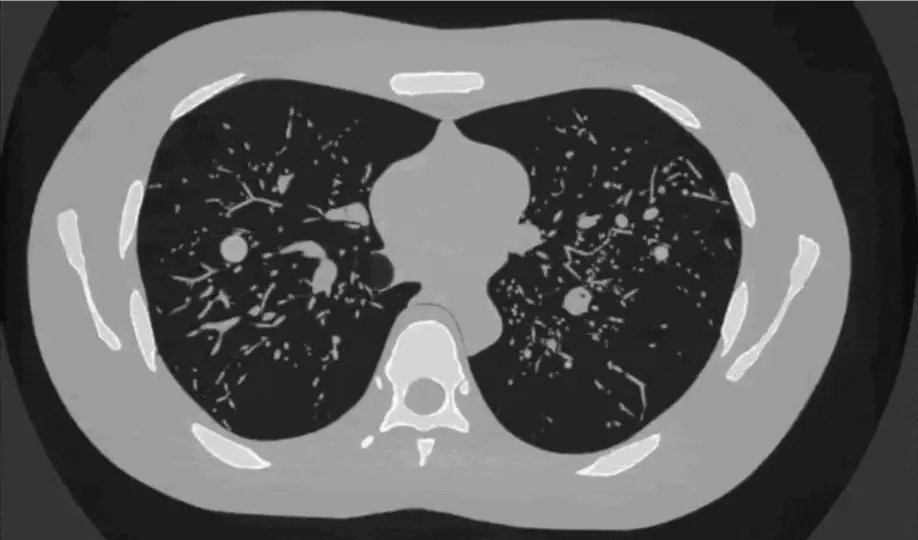

Using a LungMan phantom and the Eiger2 detector from DECTRIS, we showed that strong phase-contrast effects are present at the high energies needed for lung imaging, and optimised the imaging parameters to achieve a dose reduction factor of 160 compared to conventional absorption imaging.